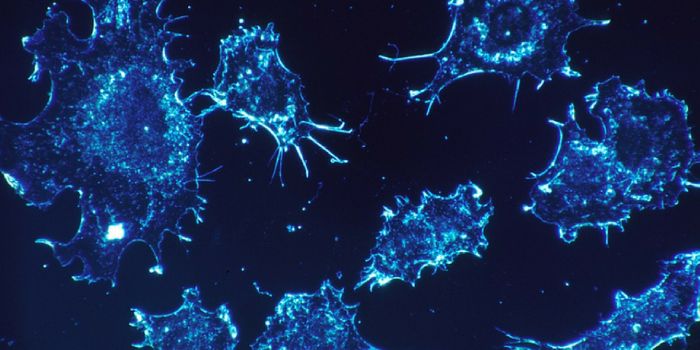

NOV 29, 2023CancerThe CAR-T Revolution: Developing T Cells into Cancer Assassins Cancer has long been a formidable foe, but recent ...